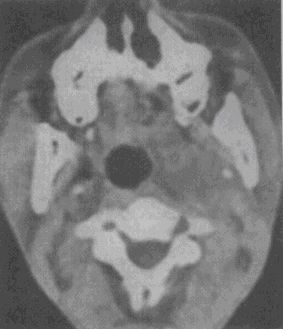

1.男性,50歲。涕中帶血絲1個月余,無發熱及咽部腫痛。CT檢查見圖所示,應首先懷疑以下何種疾病

A.鼻咽癌

B.咽旁膿腫

C.咽部淋巴結炎

D.喉癌

E.神經纖維瘤

正確答案:A解題思路:鼻咽癌病理上主要包括鱗狀細胞癌、腺癌、泡狀細胞癌和未分化癌。按其發展方向可分為上行型、下行型和混合型。